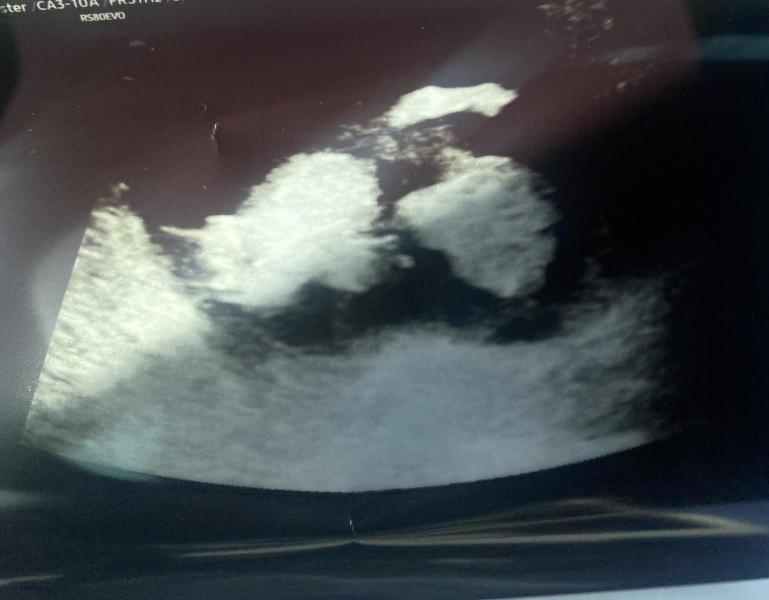

ForeverHopeful67 · 15/02/2024 20:50

Had my "12 week" scan today ladies! Here they are putting their middle finger to the world already 🤣

I'm more around the 11 week mark so have to be rescanned in two weeks, I think it's also because of my tilted uterus as they struggled to get accurate measurements but all looked good and little one was so active!

Feels very real now!!